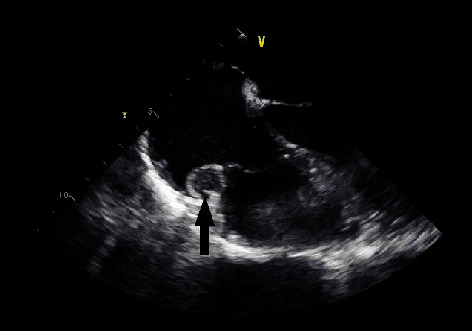

副神经节瘤是肾上腺外染色质细胞瘤。这些肿瘤中有一小部分可以在胸腔中发现,当在心脏中发现时,通常在左心房。在这个病例报告中,我们讨论了一个有SHDB突变的几个副神经节瘤病史的人,他在右心房发现了两个心脏副神经节瘤。

Paragangliomas are extra-adrenal chromaffin cell tumors. A small percentage of these tumors can be found in the thoracic cavity and, when in the heart, are typically in the left atrium. In this case report, we discuss the case of an individual with a history of several paragangliomas with the SHDB mutation who was found to have two cardiac paragangliomas in the right atrium.